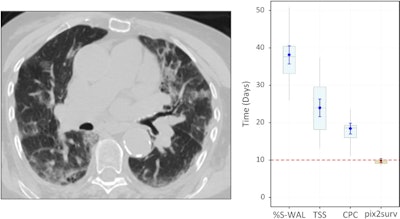

Predicted overall survival time (mortality) of a 67-year-old male who expired 10 days (red dotted line on the plot on the right) after the chest CT examination. The image on the left shows a representative example of the CT images. The plot on the right shows the predicted survival times (circles) by pix2surv and the image-based reference predictors (percentage of well-aerated lung parenchyma, total severity score, crazy paving and consolidation on CT, and lab tests) and with 95% confidence interval bars superimposed on the boxplots that represent the bootstrap results. Shared via Creative Commons license.The authors believe that their model could also be utilized for other diseases.

Using a bootstrap-based evaluation involving over 100 bootstrap replicates, the researchers compared the performance of pix2surv and four other predictive methods: lab tests, visual assessment of CT for a total severity score, visual assessment of CT for crazy paving and consolidation (CPC), and semiautomated assessment of the percentage of well-aerated lung parenchyma.

The model's prognostic performance for estimating the disease progression and mortality of patients with COVID-19 was significantly better (p < 0.0001) than those based on established laboratory tests or existing image-based visual and quantitative predictors, according to the researchers.